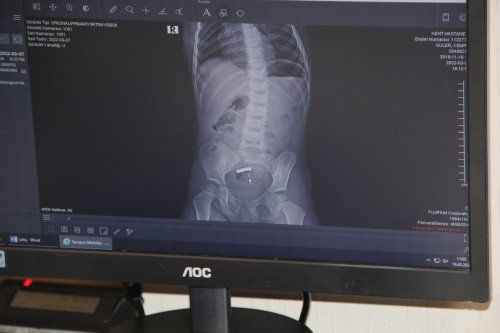

İzmir’in Aliağa ilçesinde yaşayan iki çocuk sahibi muhasebeci Nurdan (38) ve Makine Mühendisi Ali Güler (39) çifti, oğulları Mete’ye “Zeka küpü” diye satılan, manyetik mıknatıslardan oluşan oyuncak aldı. Geçtiğimiz 6 Mart’ta ağabey Mete bu oyuncakla oynarken ona kardeşi Cemre de katıldı. Mete, babasına Cemre’nin ağzına mıknatıs götürmüş olabileceğini söyledi. Cemre’nin de “yuttum” demesi üzerine çift kızlarını gözlem altına aldı. Bir tane mıknatıs yutmuş olabileceği ihtimali üzerine Cemre’nin dışkı yoluyla bu mıknatısı çıkarabileceği düşünüldü, ancak ertesi akşamüstü Cemre’nin kusmaya başlaması ve karnının ağrıdığını söylemesi üzerine aile hiç zaman kaybetmeden İzmir’e geldi ve Kent Hastanesi’ne başvurdu. Çekilen röntgende Cemre’nin birden fazla mıknatıs yuttuğu saptandı. Hemen ameliyata alınan Cemre’nin bağırsaklarından 5 mıknatıs çıkarılırken, bağırsağının delindiği belirlendi. Bağırsağının 10 santimetre kadarlık bir bölümü alınan Cemre, daha 2,5 yaşında ameliyat masalarıyla tanışırken, 5 gün yattığı hastaneden şifayla taburcu oldu.

Bu kazaların ölümcül sonuçlara yol açabildiğine dikkat çeken Doç. Dr. Özdemir, Cemre'nin bağırsağından yaklaşık 10 santimetrelik kısmı almak zorunda kaldıklarını belirterek, “Hastayı gördüğümde şiddetli karın ağrısı vardı, kusuyordu. Daha önceki deneyimlerim dolayısıyla çoklu mıknatıs yuttuğu için aşağı yukarı ne olduğunu tahmin ettim. Genellikle bağırsak tıkanıklığı ve bağırsak delinmesi tablosuyla karşılaşıyoruz. Aileye kısa sürede ameliyat edilmesi gerektiğini söyledik. İki buçuk yaşında bir çocuk için bağırsak tıkanıklığı ve delinmesi çok ağır tablolardır. Yetişkinler için de öyle; ama 2,5 yaşında olunca çok daha kötü şekilde önümüze geliyor. Ameliyatta tahmin ettiğimiz gibi 4 mıknatıs bir bağırsakta, 1 mıknatıs diğer bağırsakta dururken bunlar birbirlerini bulmuşlar. Çok da güçlü mıknatıslar olduğu için aradaki iki bağırsak duvarı zamanla eriyip mıknatısların birbirine bağlanmasına neden olmuş. Bir bağırsak kısmında 3 delik vardı. Yaklaşık 10 santimetre kadar bağırsağı çıkarmak durumunda kaldık, diğer tarafta ise bağırsaktaki deliği onardık” dedi.